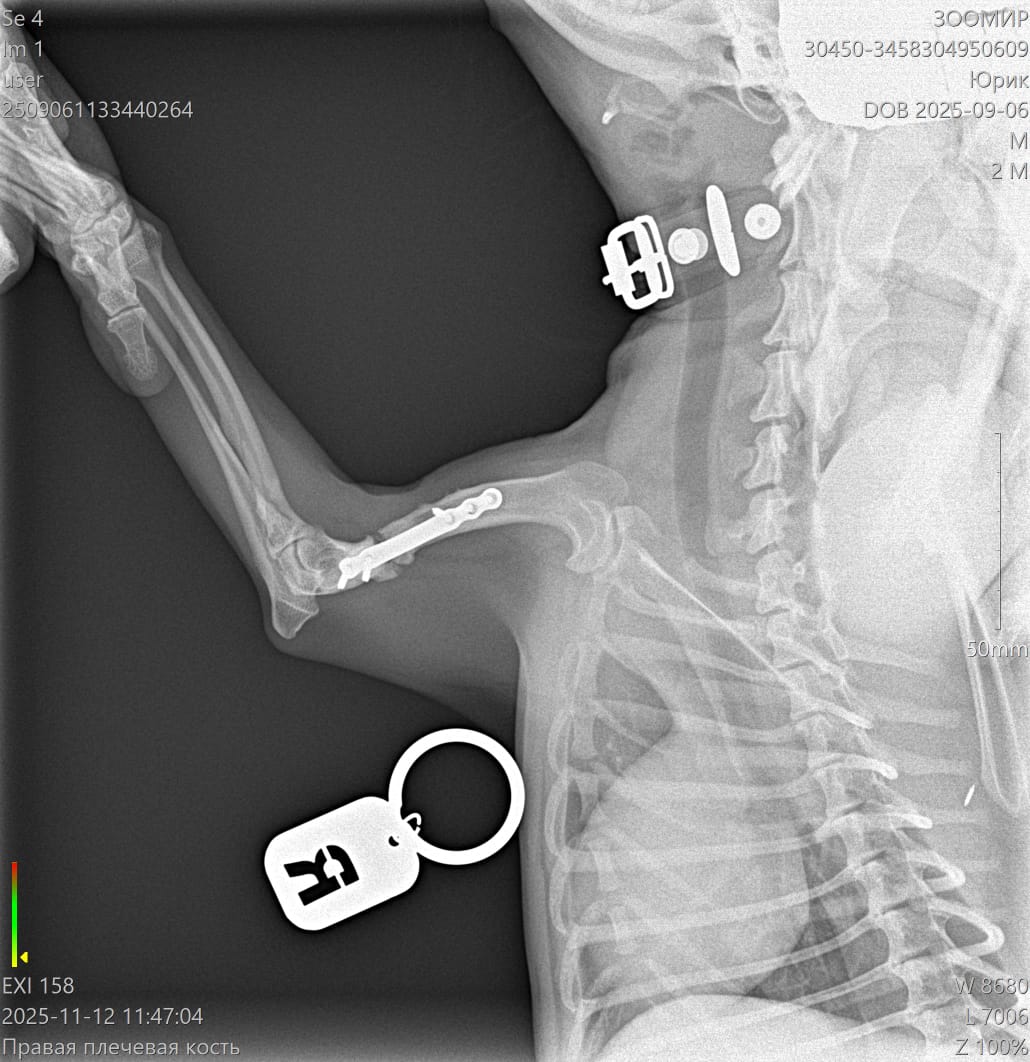

Юрик съездил сегодня на контрольный рентген.

Больная лапа вернула свой нормальный размер и окрепла.

Ходит и тянет на всех четырех. Быстро летает по пересеченной местности - бережет. Видимо не удобно, что покороче.

Мозоль ОБРАЗОВАЛАСЬ. По центру она еще не очень плотная, но кость срослась.

Как Ольга паразита не оберегала, но на рентгене оказалась чуть погнутая пластина и один сломанный винт.

Снимать ничего не будем из конструкции, если не начнет отторгаться или двигаться.

2 рентгена и осмотр АН обошлись в 2600₽ ( это стоимось 2 снимков).

Юрик. Взгляд изнутри